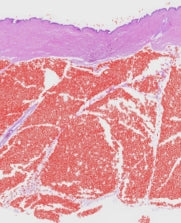

The stimulation of hyaluronic acid slows the oxidation of the skin due to aging, it promotes the absorption of active ingredients and is able to retain up to 1,000 times its weight in water which contributes to good hydration of the skin. skin. The increase in the secretion of adiponectin boosts the synthesis of collagen in the skin to maintain its suppleness. Study conducted in topical application of absolute concentration anti-aging face serum on human skin explants from 10/19/2020 to 03/30/2021. The objective of the study is to assess the benefits of the product on skin biology by measuring the production of compounds in the skin's extracellular matrix, the anti-inflammatory properties as well as the effect on the biology of the hypodermis.

Skin adiponectin stimulation